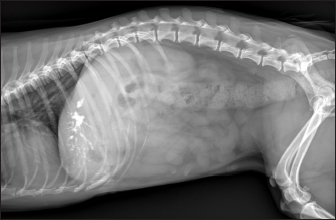

As shown in Table 5, the most represented localization was the widespread one, while we noted a prevalent localization on the right lobes compared to the central and the left lobes. In two dogs (6.2%) that showed sub-centimetric or centimetric foci of mineralization distributed in a branched pattern, we found diffuse intrahepatic biliary tree ectasia. Only two dogs underwent a radiographic examination of the abdomen: in both cases, the site of IBTM observed ultrasonographically was confirmed by radiographs, and in particular, they were localized on the ventral portion of the right lobes with a branched mineralization pattern. In both cases, IBTM was sub-centimetric or centimetric (Fig. 5).

Fig. 5. Right lateral abdomen radiograph. Sub-centimetric and centimetric IBTM are visualized as radiopaque structures superimposed on the hepatic silhouette in a dog.